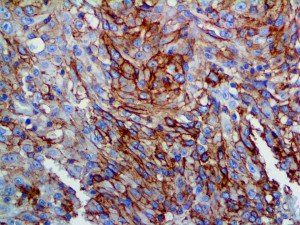

The first cytokines released are interleukin 1β (IL-1β) and tumor necrosis factor-α (TNF-α), which attract a variety of circulating white blood cells (WBCs) to the infection site, including neutrophils, monocytes, macrophages, and natural killer (NK) cells. This response, along with the antipathogenic chemicals released by these cells (i.e., complement), comprise the innate immune response. These cells directly attack the invading pathogen and also release additional cytokines, chief among them interleukin-1 and 6 (IL-6). IL-6 is essential for invoking the adaptive immune response, which calls T-cells, B-cells, and T helper (Th) cells to the infection site. IL-6 also stimulates further recruitment, proliferation and activation of macrophages.

It is the ICU physician who is most likely to witness one of the deadliest manifestations of the abnormal immunological response, the cytokine storm syndrome (CSS). This response is also referred to by some as the cytokine release syndrome (CRS). CSS is characterized by continuous activation and expansion of macrophage and lymphocyte populations, which secrete large amounts of cytokines, causing the cytokine storm. This massive cytokine release is akin to hemophagocytic lymphohistiocytosis (HLH) disease, a syndrome characterized by initial unchecked and persistent activation of cytotoxic T lymphocytes and NK cells.

This activation induces inflammatory monocytes to highly express IL-6, starting a localized and then systemic cascade effect that results in hyperproduction of IL-6, which accelerates the inflammatory process. Because IL-6 also increases vascular permeability, excessive levels cause blood vessels to become very leaky. This, along with clotting factors released from vascular endothelial cells, stimulates the coagulation cascade, resulting in microthrombosis (tiny clots), which leads to ischemia and tissue death of the kidney, intestines, heart, liver, brain and extremities.